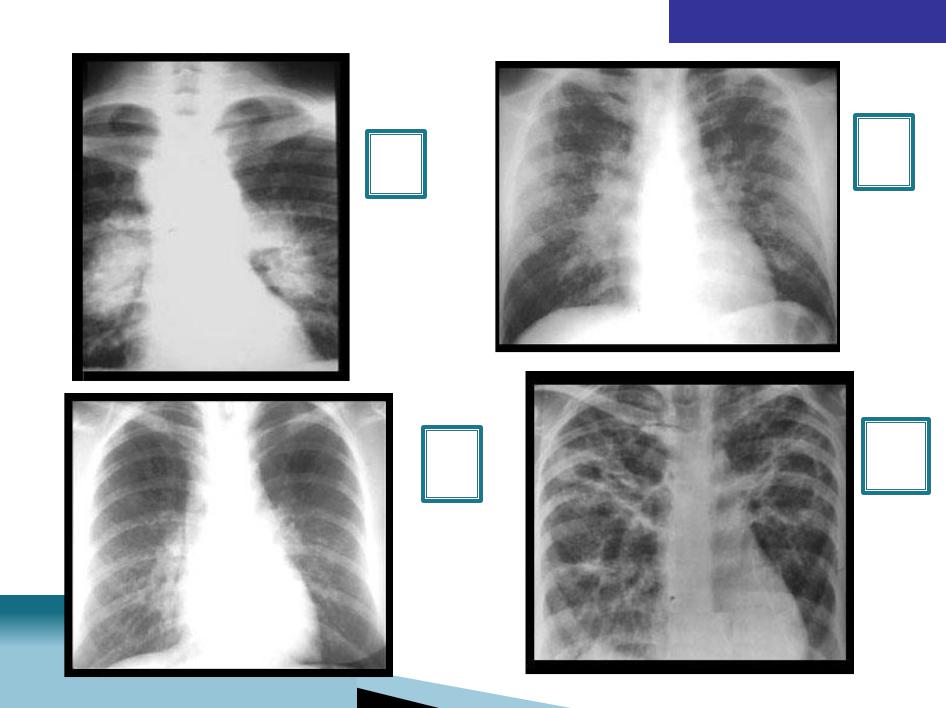

РЕНТГЕНОГРАФИЯ

II

I

IV

III